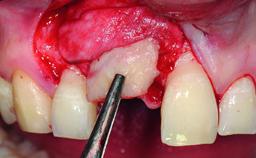

A 49-year-old female patient was referred for implant therapy to replace the upper right central incisor (tooth 11). The tooth had been assessed by an endodontist who diagnosed a vertical fracture of the root. The tooth had a hopeless prognosis and needed to be extracted. The patient was healthy and was not taking any medications. She was allergic to penicillin. The patient had high esthetic demands but her expectations were realistic. The extraoral examination revealed no facial asymmetries. The right temporomandibular joint demonstrated an opening click but was otherwise asymptomatic. The lip line was high with a significant gingival display.